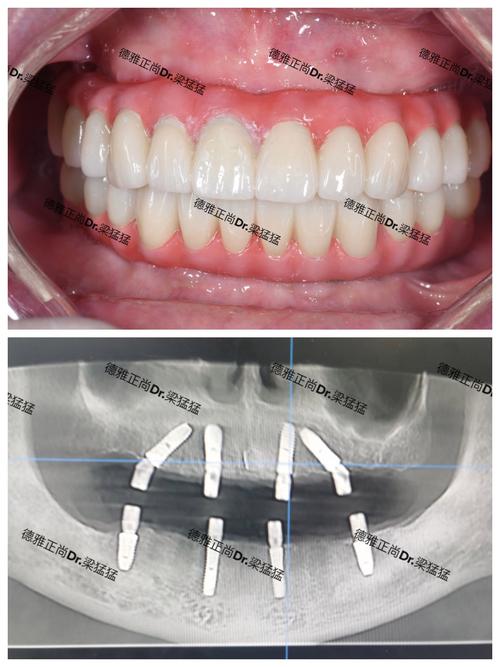

骨结合完成后过渡期(种植体稳定后至最终修复体戴入前,约2-4周)

当种植体与骨结合达到稳定状态(通过X光检查确认),医生会取模制作最终修复体,此阶段需戴用临时过渡冠,主要目的是:

- 确保牙龈形态自然:临时冠的边缘和形态可调整牙龈高度和弧度,避免最终修复体戴入后牙龈萎缩或增生。

- 测试咬合舒适度:通过临时冠的试戴,观察患者咬合是否受力均匀,避免最终修复体出现早接触或咬合创伤。